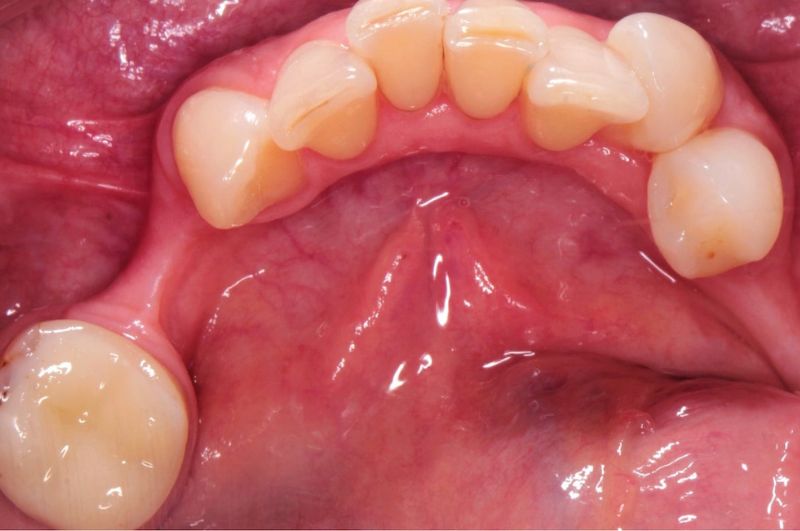

Implanty stomatologiczne w dzisiejszych czasach są najlepszą metodą odbudowy braków zębowych. Obecnie implantologia daje możliwości nie tylko łatwej, ale również bezbolesnej odbudowy utraconego uzębienia, przez co nie dochodzi do dalszej destrukcji tkanek w jamie ustnej.

Implanty przywracają piękny uśmiech pacjentom, ale przede wszystkim odtwarzają prawidłowe funkcje zgryzu. Wiele osób jednak zastanawia się, po jakim czasie od wyrwania zęba można wszczepić implant.

Implantacje natychmiastowe to zabiegi wszczepiania implantów bezpośrednio bo zabiegu ekstrakcji zęba. Umożliwiają wprowadzenie implantu w miejsce po usunięciu zęba podczas jednej wizyty. Bardzo często implantacja natychmiastowa nie wymaga dodatkowego cięcia, gdyż wykorzystywana jest luka w wyrostku zębodołowym powstała po wyrwaniu zęba.